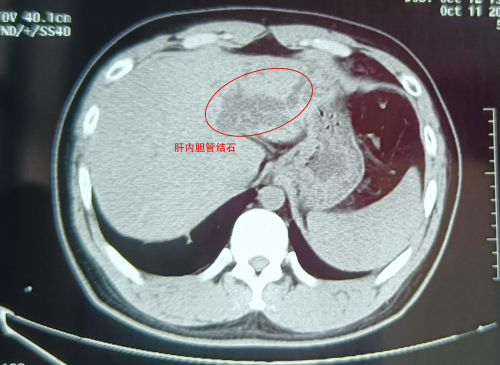

武漢的劉先生怎么也沒想到,看似普通的腹痛,竟險(xiǎn)些讓自己丟了肝!近日,這位肝膽系統(tǒng)布滿結(jié)石的“小黃人”,緊急求助于武漢京都結(jié)石醫(yī)院。幸運(yùn)的是,因?yàn)槭中g(shù)處理得當(dāng),劉···